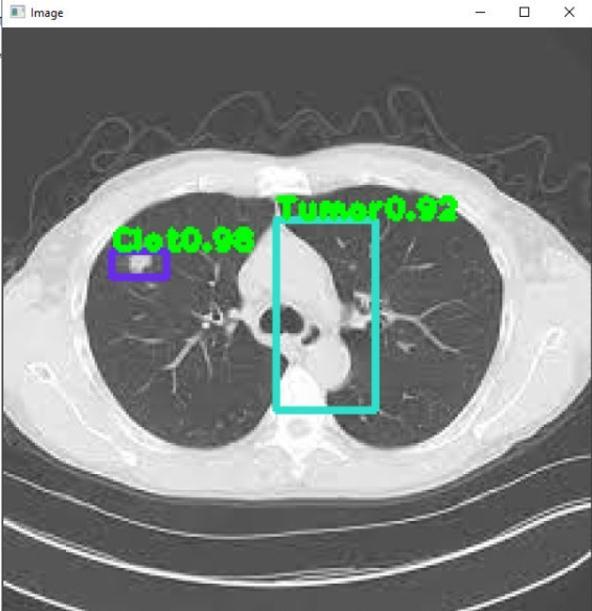

Fig 3 :TomorDetectedinLungs Fig 4 :ClotDetectioninLung Fig 4 :Clot&TumorDetectioninLung Fig – 5 :TumorDetectioninLung

finaloutcome.